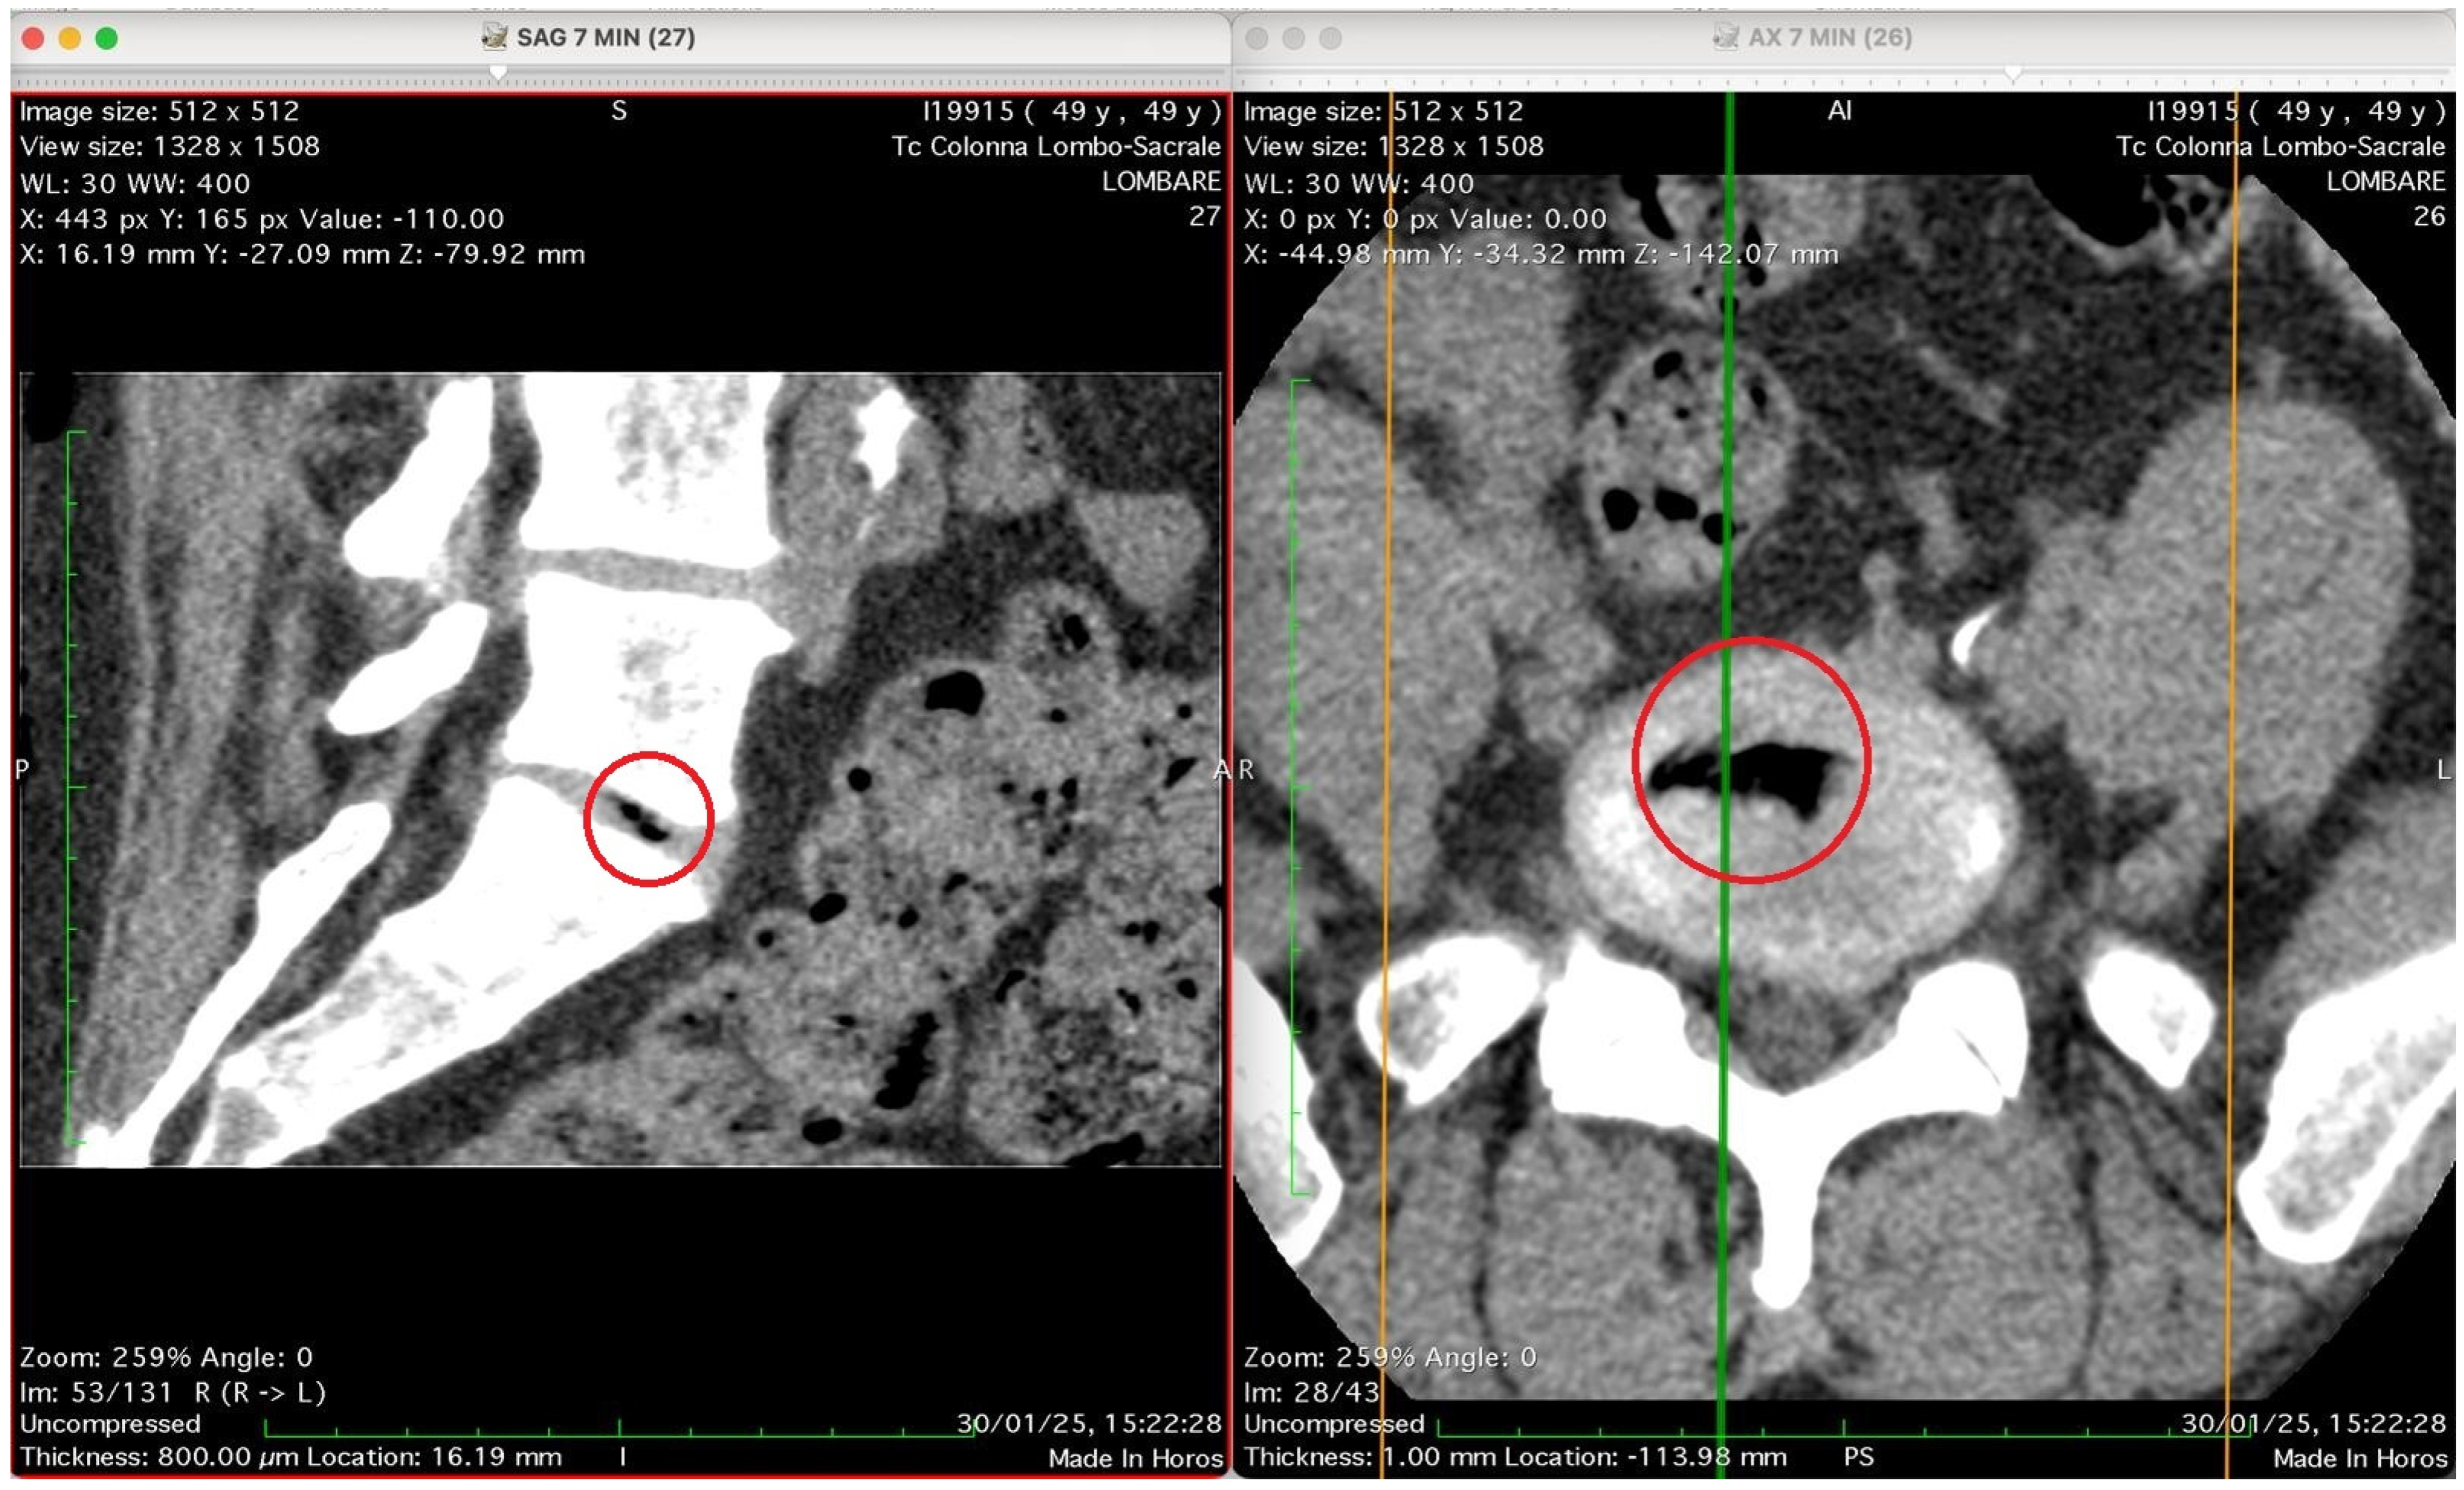

Figure 2, Figure 3, Figure 4 and Figure 5 show four computed tomography (CT) scans, along a time-course analysis, of the lumbosacral spine, visualized in sagittal (left) and axial (right) planes, from an exemplificative male patient (49 years) with L5-S1 herniated disc, undergoing an experimental setting of oxygen–ozone therapy via the intramuscular approach (Revolution™ CT, GE-Healthcare, Chicago, IL, USA). The very low-density ozone gas (hypodense, dark black within cred circles), spreads over the intervertebral disc within the time course of less than 10–20 min, assessing that ozone in the oxygen medium really reaches the morpho-functional area where the herniated disc is present in short times. A possible explanation is provided in the next paragraph.

Figure 2 shows two computed tomography (CT) images of the lumbar spine from a lumbosacral CT scan at time 0 (“Tc Colonna Lombo-Sacrale”), displayed in two standard planes. The left panel (SAG 7 MIN), shows a sagittal reconstruction through the lumbar region. The vertebral bodies, intervertebral discs, and spinal canal are seen in longitudinal profile. Gas-like hypodense areas (black regions) are still not visible in the intervertebral disc spaces, as this is the time 0, when present these correspond to intradiscal gas, consistent with vacuum phenomenon or possible gas introduced by percutaneous-intramuscular injection. The soft tissues and paravertebral structures are also visible. Right panel (AX 7 MIN) shows an axial slice at a corresponding lumbar level. The spinal canal is centrally located, surrounded by vertebral bone. The alignment of the green and orange cross-reference lines indicates the plane correspondence between sagittal and axial images. Technical details (as annotated in the image): Matrix size: 512 × 512 Window/Level (WL/W): 30/400 (bone-soft tissue contrast) Slice thickness: 0.8 mm (reconstructed to ~16 mm view) Scan date: 30 January 2025 Interpretation summary: The image pair represents a CT lumbosacral segment showing intradiscal and paravertebral gas, likely associated with degenerative disc disease or following paravertebral oxygen–ozone therapy. The correspondence between sagittal and axial planes allows correlation of gas location relative to the disc and vertebral bodies.

This figure shows two CT images of the lumbosacral spine obtained in sagittal (left) and axial (right) planes from a CT lumbosacral study (Tc Colonna Lombo-Sacrale). Both images are co-registered (cross-referenced by coloured guide lines) and highlight the same anatomical level, marked with a red circle. Left panel (SAG 7 MIN, slice 27): This sagittal reconstruction depicts a clear intradiscal gas pocket at an intervertebral level (most probably L4–L5 or L5–S1). The gas appears as a sharply defined, elongated hypodense linear area (black) within the intervertebral disc space. The morphology suggests that the gas has collected along a fissure of the annulus fibrosus or within a cleft of the nucleus pulposus, typical of either a vacuum phenomenon from disc degeneration or gas migration following paravertebral intramuscular oxygen–ozone injection. The vertebral endplates and adjacent vertebral bodies appear intact, with no signs of osteolysis or fracture. Right panel (AX 7 MIN, slice 26): The axial CT slice confirms the presence of a gas inclusion in the centre of the discal space, delineated by the red circle. The gas pocket has very low attenuation (near air density) and a regular contour, lying entirely within the confines of the disc, without extension into the epidural space or paravertebral soft tissues. The vertebral canal is preserved, and no evidence of epidural or foraminal gas or mass effect on neural structures is seen. Technical data (from the annotations): Image matrix: 512 × 512 WL/W: 30/400 Slice thickness: 0.8 mm Acquisition time: 30 January 2025, 15:22:28. Interpretation summary: The paired sagittal and axial CT images demonstrate a well-defined intradiscal gas pocket consistent with intradiscal migration of gas, likely due to paravertebral oxygen–ozone diffusion through the annular fissures rather than direct intradiscal injection. The finding supports a mechanism of gas penetration via micro-fissures without needle breaching of the disc, a phenomenon occasionally observed after paravertebral oxygen–ozone therapy or in degenerative disc disease.